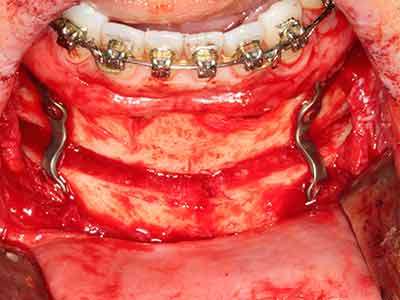

Fig. 13: Adequate irrigation with the 4-mm residual bone width is essential for this 52-year-old patient during the bone splitting.

Fig. 14: Placement of four tapered RSX implants (Bego Implant Systems, Bremen).

Fig. 15: The one-year follow-up x-ray examination shows stable conditions at the bone level.

Fig. 16: The intraoral conditions are also stable with embedding of the implants in keratinized gingiva.